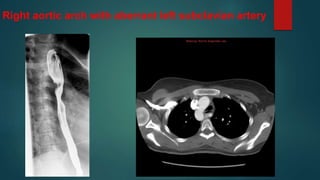

Right aortic arch with aberrant left subclavian artery

• #7 First vessel from the arch is the left commmon carotid artery. Bilateral calcified pleural plaques. Thrombosed ligamentum arteriosum. Kommerell's diverticulum/dilatation of the origin of the left subclavian artery causes compression of the left brachiocephalic vein resulting in contrast entering the heart via alternative routes